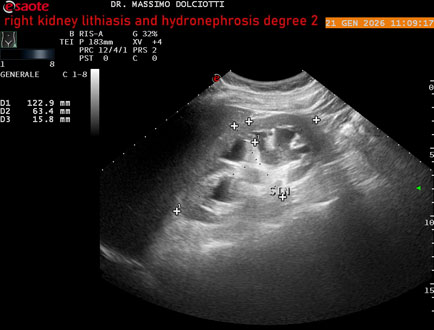

Data inserimento: 22/01/2026

Ecografia del: 21/01/2025

Strumento: Esaote MyLab Eight

Sonda: Convex Multifrequenza 1-8 MHz

Età Paziente: M 27 anni

Motivazione dell'esame: dolore al fianco destro da 3 mesi.

Commento all'esame: le immagini ed il video documentano il rene destro in sede, con ecostruttura disomogenea per evidenza, alla pelvi renale, di immagine iperecogena delle dimensioni di 16,2 mm, con cono d'ombra posteriore, da ricondurre a litiasi ed una formazione simile, di minore entità, al polo inferiore, delle dimensioni di 6,8 mm. Rene dx con diametro longitudinale di 122 mm (v.n. 90-120 mm) x 63 mm e parenchima renale dello spessore di 15 mm (v.n. > 13 mm). Rene dx con idronefrosi di 2° grado.

Conclusioni: litiasi e idronefrosi di 2° grado al rene destro (lithiasis and second-degree hydronephrosis of the right kidney).

In collaborazione: Dr.ssa Marica Manfredi - Ancona, Dr. Ilir Qose - Ancona

Presentazione: Dr. Massimo Dolciotti - Ancona

Elaborazione digitale: Andrea Dini - Ancona